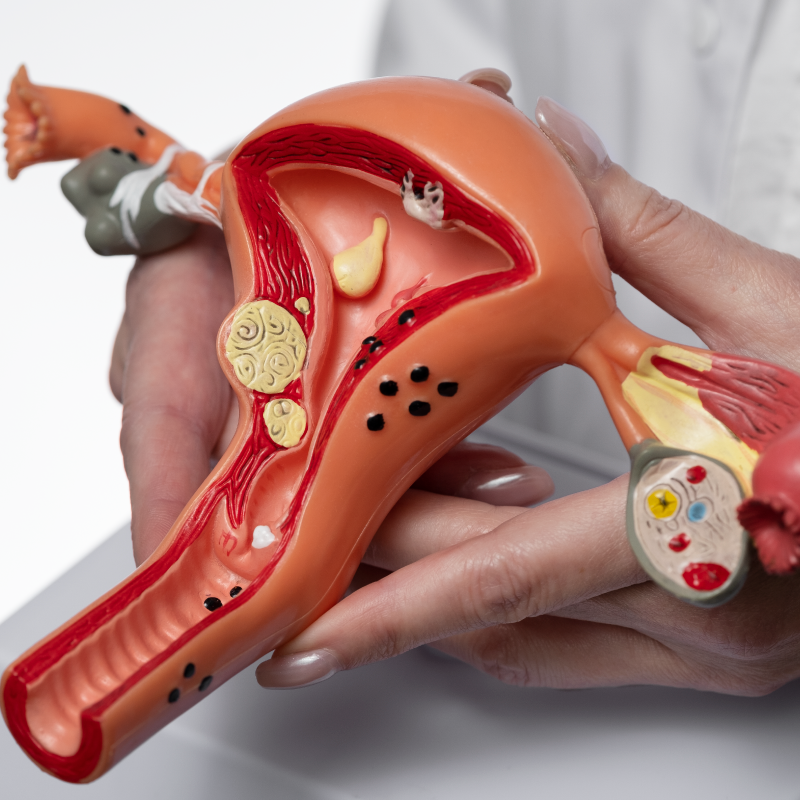

Nuestras especialidades

Comprometernos a cuidar y proteger la salud de todos nuestros pacientes basados en principios de: calidad, profesionalismo y ética, cuyo objetivo es mejorar la calidad de vida de toda una comunidad.

Nuestros servicios

Para mejorar la experiencia de todos nuestros pacientes contamos con: Exámenes de Laboratorio, Rayos X, Ecografía y Farmacia.